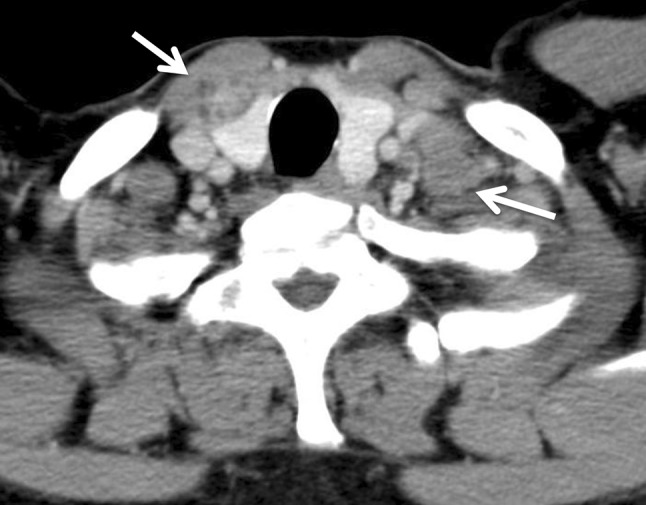

Fig. 2.

Cervical to abdominal CT showed swelling of Virchow’s lymph node (right arrow) and tumor in the thyroid gland (left arrow)

A 53-year-old male presented with a chief complaint of a bloody stool. Colonoscopy showed circumferential ulcer in cecum, and abdominal computed tomography (CT) showed wall thickening in cecum and enlarged lymph nodes. No metastasis was revealed in the liver and lungs. Radiographic contrast enema revealed apple-core-sign in cecum. Mild anemia was shown (Hb 11.2 g/dL), and carcino-embryonic antigen (CEA = 5.2) and carbohydrate antigen 19-9 (CA19-9 = 308.9) were elevated in blood examination. The preoperative diagnosis was colon cancer, C, SS, N2, H0, P0, M0 Stage IIIb by the Japanese Classification of the Colorectal Carcinoma (JCCC) [1]. Right colectomy with D3 lymph node dissection was performed (Fig. 1). Histological examination showed colon cancer, C, type 2, 45 × 30 mm, 1/2 circ, tub2 > tub1 > por1 > por2, SE, int, ly2, v1, N3 [No201(10/13), 211(0/4), 202(1/2), 203(1/3)], H0, P0, M0, PM0, DM0, RM0, Stage IIIb by JCCC. After the operation, the patient received chemotherapy with Capecitabine regimen (starting dose: Xeloda® 4200 mg/body orally on day1–14, every 3 weeks). During 3 cycles of Capecitabine regimen, due to the onset of icterus (Grade2), we managed to continue Capecitabine regimen with the extension of interval period and dose reduction. But after 6 cycles of Capecitabine regimen, icterus was exacerbated. The chemotherapy was aborted. After 1 year later, CT detected swelling of Virchow’s lymph node and tumor in the thyroid gland (Fig. 2). Positron emission tomography showed that increased standardized uptake values (SUV) of 28.0 and 7.0 were observed in the thyroid gland tumor and left cervical region (Fig. 3). By fine-needle aspiration cytology, thyroid gland tumor was diagnosed as papillary carcinoma and Virchow’s lymph node was detected adenocarcinoma which was metastasis of cecal cancer. We diagnosed, thyroid papillary carcinoma, T3, N1b, M0, Stage IVa and recurrence of cecal cancer in Virchow’s lymph node. In selecting surgical therapy or chemotherapy, chemotherapy has side effects of icterus due to Capecitabine, there was a possibility that chemotherapy was difficult to continue. In surgical treatment, cervical dissection was possible in the treatment of thyroid papillary carcinoma, and no organ metastasis in the whole clinical course and no other sites of nodal metastasis except Virchow’s node at the time of the recurrence. From these points, we thought that surgical treatment was better than chemotherapy. After informed consent from surgeon and otolaryngologist, the patient wished surgical treatment. Total thyroidectomy and cervical lymph node dissection was performed. Finally histological examination revealed that Virchow’s lymph node was moderately differentiated adenocarcinoma as a metastatic cecal cancer (Fig. 4). After the operation, the patient received chemotherapy with 6 cycles of FOLFOX regimen (5-FU bolus 720 and 4250 mg/body, leucovorin 360 mg/body and oxaliplatin 150 mg/body). And the patient had taken UFT/LV for 30 months. After UFT/LV regimen, the patient selected follow-up without chemotherapy. Now he has no recurrence and keeps his quality of life high. He has been surviving for 80 months since the first operation (Fig. 5).